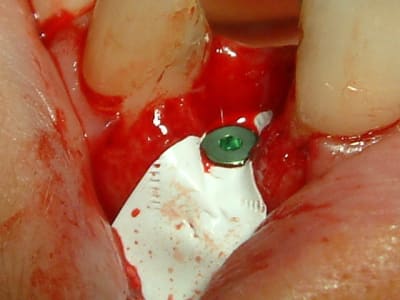

ce matin, j'ai essayé le cerasorb avec une membrane Tefgen... qui a une expérience de ces matériaux?

voici les clichés et j'ai hâte de voir ce que çà va donner..

@+

(oups, ouvrir dans l'ordre cliché 31, 32 etc...)

mes clichés sont pris par moi même avec un fuji finepix 7000 en mode super macro et lumière du scialytique (et avec la résolution la plus basse que propose cet appareil)

pour la stérilité je troue le côté papier d'une gaine pour laisser passer l'objectif puis je stérilise cette gaine à l'autoclave. ci joint un cliché du dispositif.

c'est simple et efficace (le côté transparent de la gaine me laisse visualiser l'image sur l'ecran du viseur)